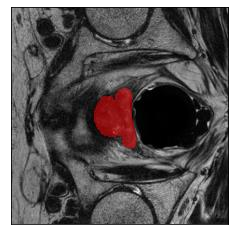

Machine learning models are typically deployed in a test setting that differs from the training setting, potentially leading to decreased model performance because of domain shift. If we could estimate the performance that a pre-trained model would achieve on data from a specific deployment setting, for example a certain clinic, we could judge whether the model could safely be deployed or if its performance degrades unacceptably on the specific data. Existing approaches estimate this based on the confidence of predictions made on unlabeled test data from the deployment's domain. We find existing methods struggle with data that present class imbalance, because the methods used to calibrate confidence do not account for bias induced by class imbalance, consequently failing to estimate class-wise accuracy. Here, we introduce class-wise calibration within the framework of performance estimation for imbalanced datasets. Specifically, we derive class-specific modifications of state-of-the-art confidence-based model evaluation methods including temperature scaling (TS), difference of confidences (DoC), and average thresholded confidence (ATC). We also extend the methods to estimate Dice similarity coefficient (DSC) in image segmentation. We conduct experiments on four tasks and find the proposed modifications consistently improve the estimation accuracy for imbalanced datasets. Our methods improve accuracy estimation by 18\% in classification under natural domain shifts, and double the estimation accuracy on segmentation tasks, when compared with prior methods.